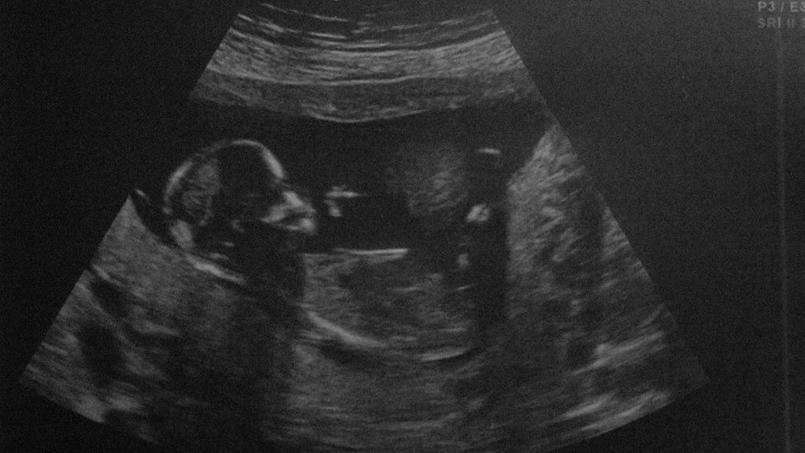

Le 26 juillet 2017, une naissance à l’hôpital de Boulogne-sur-Mer a été annoncée comme un « malheureux événement ». Elle a mis en lumière l’injonction paradoxale adressée aux personnes porteuses d’un handicap : « Prenez toute votre place dans cette société où tout est fait… pour que vous n’existiez pas ! »

Étrange échec : le bébé avait réchappé à l’« interruption médicale de grossesse » (IMG). Alors que sa mère était à son huitième mois de grossesse, une IRM ayant détecté une malformation cérébrale, des médecins avaient aussitôt « prescrit l’IMG ». L’intervention consiste à provoquer la mort du fœtus menacé d’un handicap. Ici, par un « fœticide au cordon », c’est-à-dire l’injection d’un produit létal in utero, pour provoquer la mort du bébé avant de déclencher l’accouchement d’un enfant « mort-né ». Or, voilà donc que, contre toute attente, l’enfant est né vivant. Après une succession de tel chocs, on imagine le désarroi des parents au moment où les soignants prennent soin avec eux de cette vie fragile qu’ils n’ont pas réussi à arrêter.